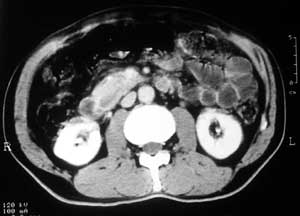

患者,男,57岁,梗阻性黄疸10余天。

这个病例胰头无明显增大,胆总管扩张明显而肝内胆管扩张更不明显,病程较短,

注意到十二指肠乳头明显突出,但尚光滑。分析以下可能性:

1、十二指肠乳头本身的病变,如乳头炎症;

2、急性乳头水肿,胆总管下端结石排石后乳头水肿;

3、壶腹部胆总管下端肿瘤累及十二指肠乳头。

十二指肠乳头粘膜慢性非特异性炎症